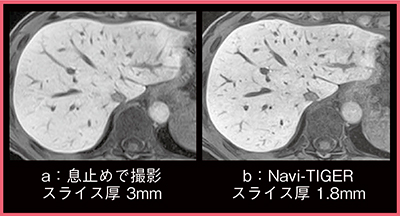

●Navi-TIGRE

上腹部領域の検査では,呼吸や心拍,消化管蠕動などによる動きが問題となるため,息止め撮像が基本となるが,なかには息止めが難しい患者もいる。TRILLIUM OVALには,横隔膜Navigatorを併用したNavi-TIGREが実装されており,これを用いることで息止め不良の患者に対して,画質の劣化を改善できる可能性がある。

図3は,息止めで撮像したスライス厚3mm(a)と自由呼吸下で撮像したスライス厚1.8mmのNavi-TIGRE(b)のEOB造影MRI肝細胞造影相の画像である。Navi-TIGREの画像は息止め撮像の画像よりも空間分解能の高い画像が得られていることがわかる。

図3 Navi-TIGRE使用の有無によるEOB造影MRI肝細胞造影相の比較